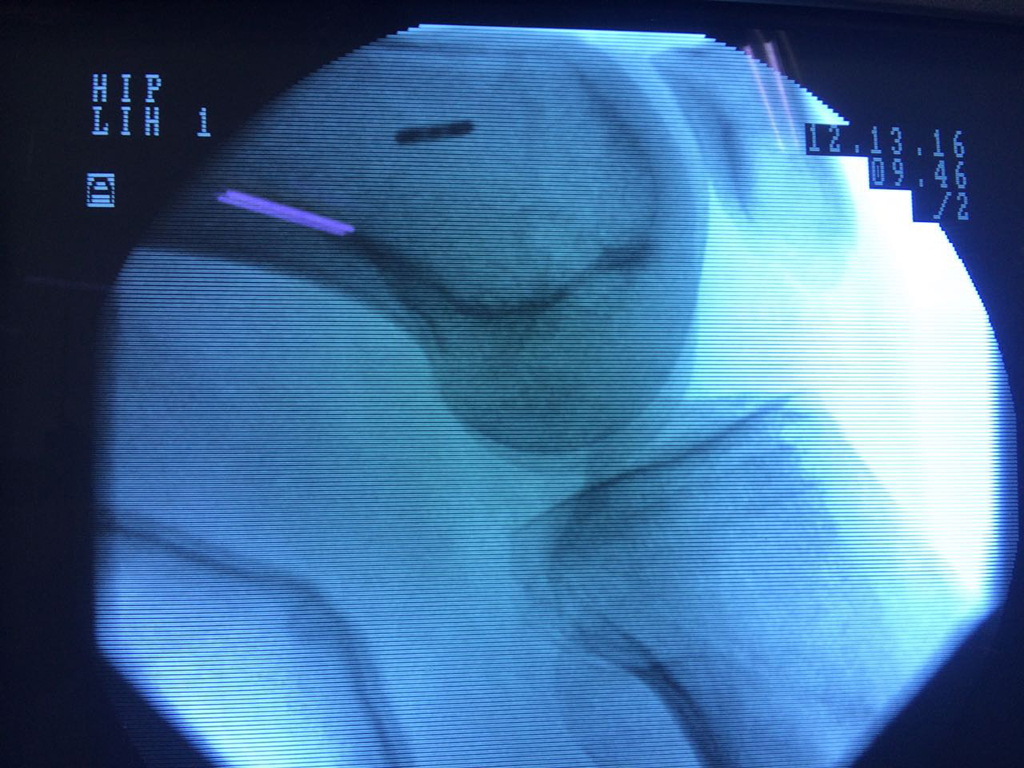

Cirugías de Cadera

La artroscopia de rodilla es un cirugía en el cual la estructura interna de la articulación es examinada ya sea para realizar un diagnostico o para realizar un tratamiento, este procedimiento se realiza utilizando un instrumento parecido a un pequeño tubo llamado artroscopio.